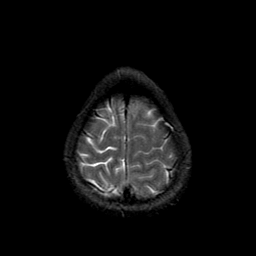

Metastatic bronchogenic carcinoma: T2-weighted MR -- Slice #20

[Home][Help][Clinical] Slice 20